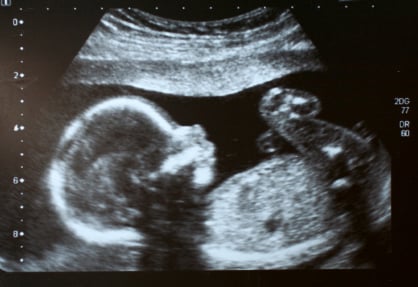

L’esame consiste in un prelievo di liquido amniotico mediante una puntura trans-addominale effettuata sotto guida ecografica. L’amniocentesi può essere eseguita sia in epoca di gestazione ‘precoce’, tra la 16° e la 18° settimana, che ne evidenzia appunto le variazioni a livello cromosomico o genetico o in fase più ‘tardiva’, dopo la 25° settimana, utile a valutare la maturità fetale.

Di norma l’esame - che deve essere preceduto da una ecografia per rilevare la vitalità del nascituro, l’epoca di gestazione o eventuali gravidanze plurime - si esegue ambulatoriamente, dura all’incirca qualche minuto e non richiede alcun tipo di anestesia.